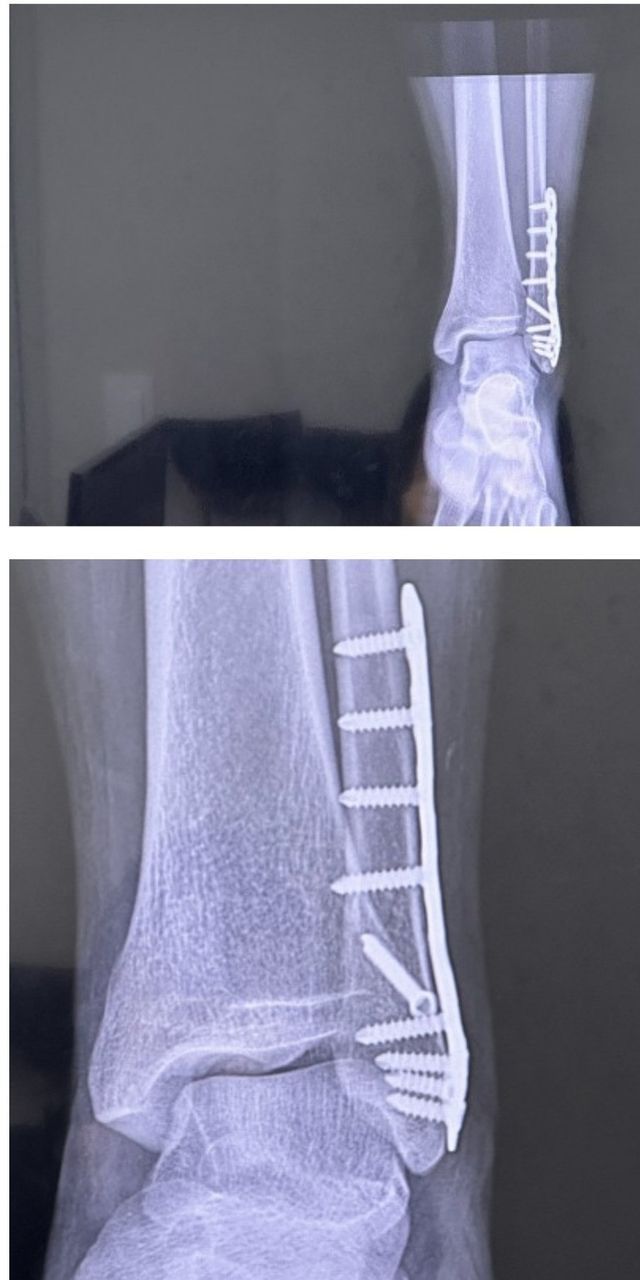

올해 1월에 부러지고 12월에 철심빼는 회복기

빙판길에서 자빠져 발목 부러져서 수술

원래는 1년뒤 철심빼기로 했는데 백수되고 한가해서 이참에 하자고 수술날짜 땡겨서 1월초로 수술 잡힘

근데 어차피 시간 남아돌아서 지금하는게 나을거같길래 또 땡겨서 12월에 수술

다음날 걸어다니는거 보고 의사 또 화들짝 바로 퇴원함